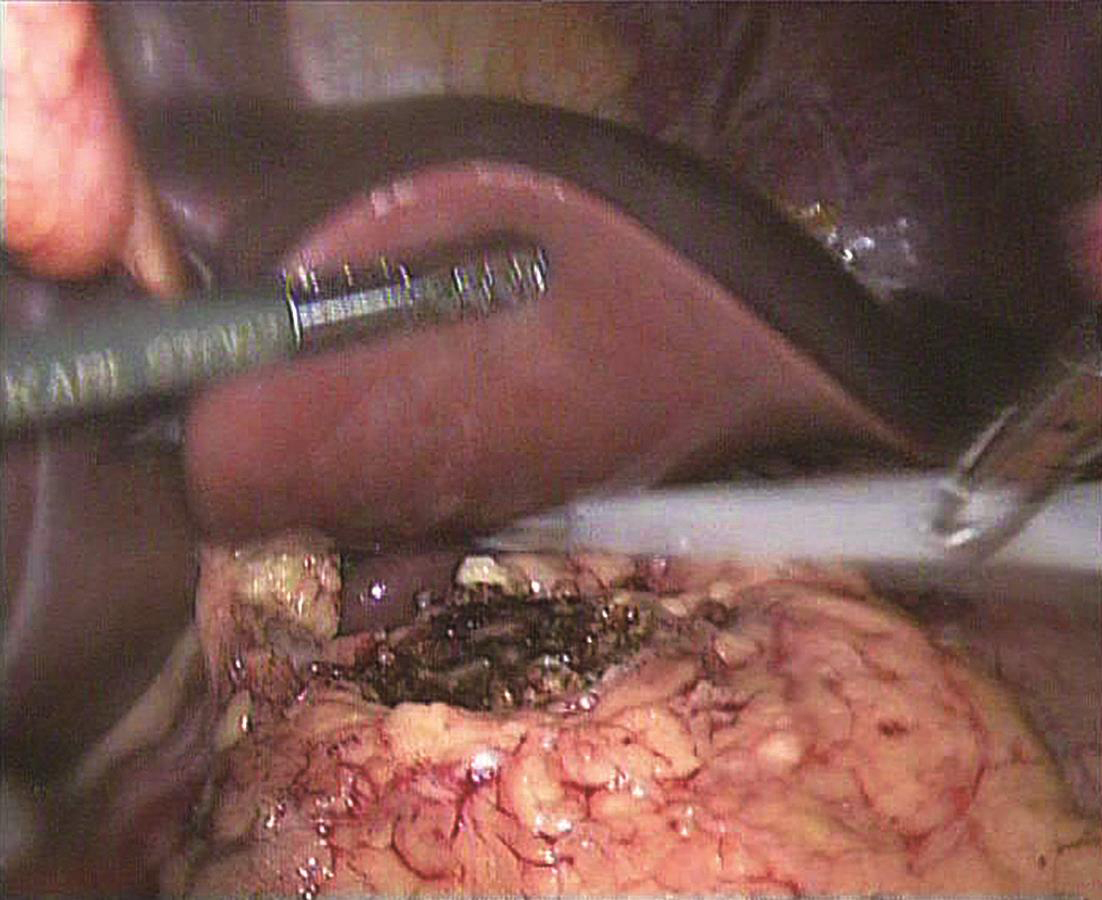

患者取平卧位,头高脚低,四孔或三孔法操作;首先自胃网膜血管弓下方横行打开胃结肠韧带(图6-1),探查胰腺颈、体、尾,必要时可打开胰腺下缘被膜,游离胰腺后方深入探查;清楚定位肿瘤后,镜下缝合肿瘤一针作为牵引用(图6-2),超声刀紧贴肿瘤,完整剜除;检查胰腺创面,选择性缝合创面(图6-3);取出标本,送冰冻,留置引流,关闭腹壁切口,术毕(图6-4)。

图6-3 超声刀完整剜除肿瘤,创面止血